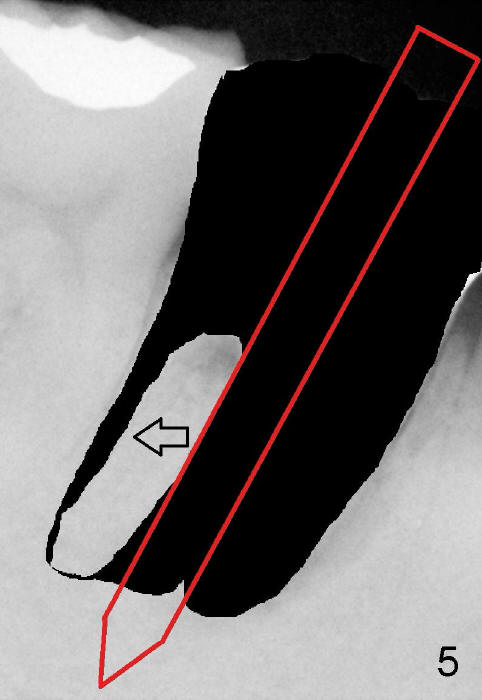

Section the septum mesiodistally with thin osteotomes so that drills and/or rounded osteotomes (Fig.4 red long arrow) will stay in the middle or mesial portion of the septum, while a part of the septum is being pushed distally (open arrow). When larger drills or osteotomes (Fig.5 thicker red long arrow) are being used, more of the septum is being pushed distally (open arrow). A 7x17 mm implant is expected to be placed in the middle of the septum or slightly into the mesial socket (Fig.6). Where does this implant end up?